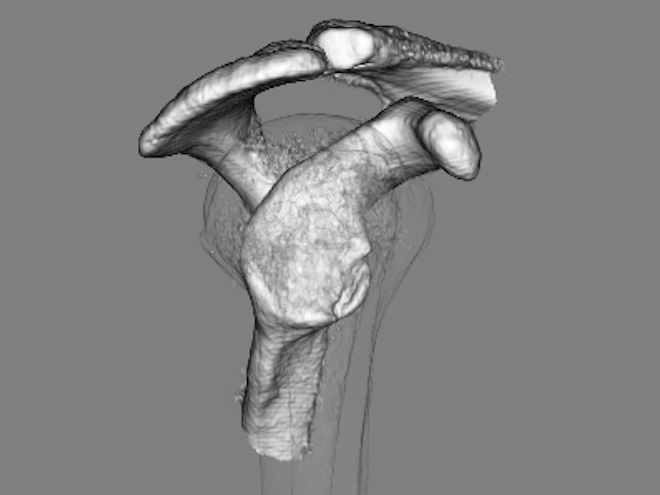

画像所見

| 術前:骨性Bankart病変 | 術後約6ヶ月 |

現病歴:ソフトテニス中に右肩関節を外転外旋位でボールを打ち返した歳に脱臼感が出現しました。佐久平整形外科クリニック受診し右肩関節唇損傷の疑いで3ヶ月間リハビリテーションを行いましたが、症状改善なく造影MRI検査施行し、結果より前方関節唇損傷・骨性Bankart病変と診断されました。疼痛・脱臼感などの症状改善がみられず競技継続を希望されたため、鏡視下肩関節唇形成術を施行し、その術中で遊離体を発見したため摘出術も施行しました。

2016年4月にソフトテニス中に右肩関節を外転外旋位でボールを打ち返した際に脱臼感があり、自己整復をした上で、佐久平整形外科クリニックを受診されました。右肩関節唇損傷の疑いと診断し約3ヶ月間リハビリテーションを行いました。しかし、症状改善がなく造影MRI検査を施行し、結果より前方関節唇損傷と骨性Bankart病変と診断されました。ソフトテニスでのサーブ・スマッシュ時の疼痛・脱臼感などの症状が改善されず、今後も競技を続けるために手術を決められました。